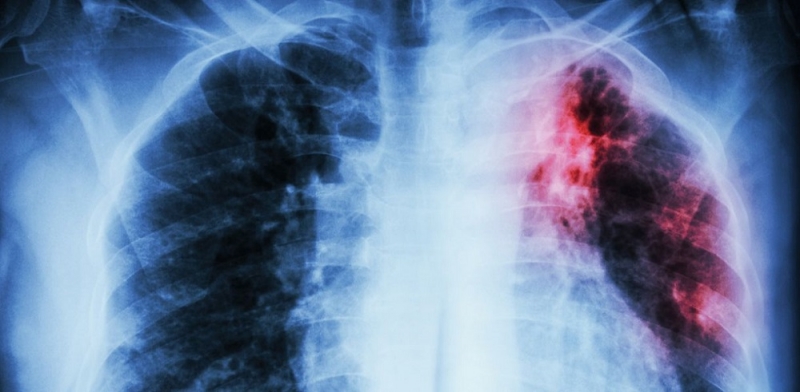

Врачи-фтизиатры отмечают рост заболеваемости среди детей. Показатель смертности от туберкулеза за 6 месяцев этого года снизился почти на 10%. Об этом…